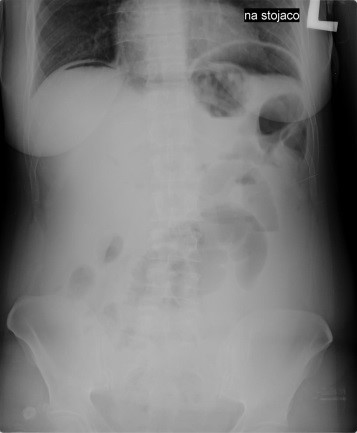

Przedstawiony obraz radiologiczny został zarejestrowany podczas badania jelita

Ilustracja do pytania 23

A. cienkiego po doustnym podaniu środka kontrastującego.

B. cienkiego po doodbytniczym podaniu środka kontrastującego.

C. grubego po doustnym podaniu środka kontrastującego.

D. grubego po doodbytniczym podaniu środka kontrastującego.